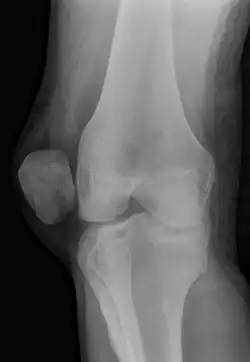

X-ray and MRI after luxation of the patella. There is a fragment and bone bruise at the medial surface of the patella and in the corresponding surface of the lateral condyle of the femur. The medial retinaculum of the patella is disrupted.